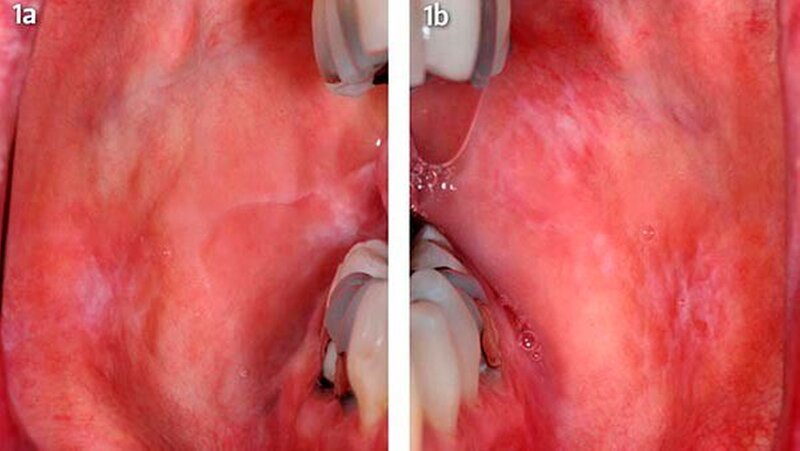

Eine 47-jährige Frau stellte sich Anfang 2012 in der Sektion für Klinische und Experimentelle Orale Medizin am Universitätsklinikum Leipzig wegen länger bestehenden typisch weißlichen Schleimhautveränderungen ohne subjektive Beschwerden vor. Nebenbefundlich bestand eine mit L-Thyroxin behandelte Hypothyreose. Beidseits im Planum buccale und in der Kieferwinkelregion rechts zeigten sich sogenannte Wickham-Streifungen mit stellenweise plaqueartigen Inseln sowie einer schwarzen Pigmentierung vestibulär von Zahn 47 (Abb. 1a, b).

Die Zungenränder zeigten mäßig weißliche papulöse Veränderungen auf. Es lag ein insuffizient versorgtes Gebiss mit zahlreichen großflächigen Amalgamfüllungen und insuffizienten Füllungsrändern mit rauen Oberflächen buccal vor. Im Orthopantomogramm zeigte sich als Nebenbefund eine kleine metalldichte Verschattung projiziert auf das mesiale obere Wurzeldrittel des Zahns 47. Dieser Befund korrespondierte mit der klinisch auffälligen Amalgamtätowierung vestibulär in der Umschlagfalte des Zahns 47. In der zahnärztlichen Allgemeinanamnese berichtet die Patientin von einer erschwerten Weisheitszahnentfernung in regio 48 vor einigen Jahren. Die Amalgamfüllungen und eine Brücke im Frontzahngebiet sind seit über 15 Jahren in situ. Die Mundhygiene war zufriedenstellend.